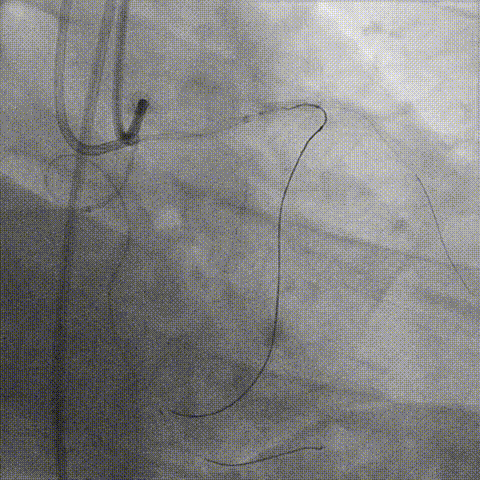

生理盐水冲洗RG3导丝(减轻导丝进入Mamba微导管手感生涩难题),顺利完成体外化

Ballon 2.5*15mm, 3.0*15mm Dilatation & IVUS check

LAD Stent Synergy 3.5*38mm

Ballon QM 4.0*12mm, 5.0*8mm Dilatation & POT

Final result: TIMI flow grade 3